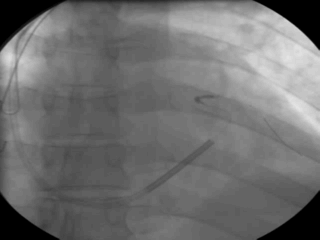

病例五

手术过程

● 冠状窦中段狭窄、成角畸形,经长鞘推送Runthrough导丝至冠状静脉心室侧后静脉远端,沿导丝送左室电极到冠状窦侧后静脉未成功,不除外Vieussen瓣阻挡

使用HI-70RQUE导丝锚定未成功

● 使用6248鞘中鞘辅助加强支撑后顺利沿导丝推送左室电极至靶血管

左室参数:

● 阈值 1.0V 阻抗 580Ω